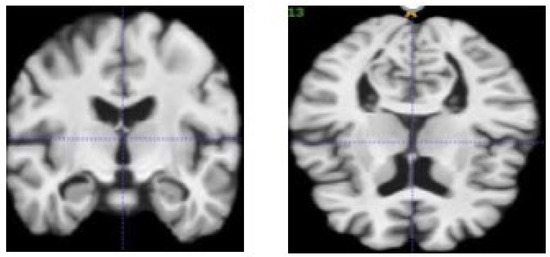

4.3.1. Image Fusion Performance

3.2. Image Fusing and Preprocessing